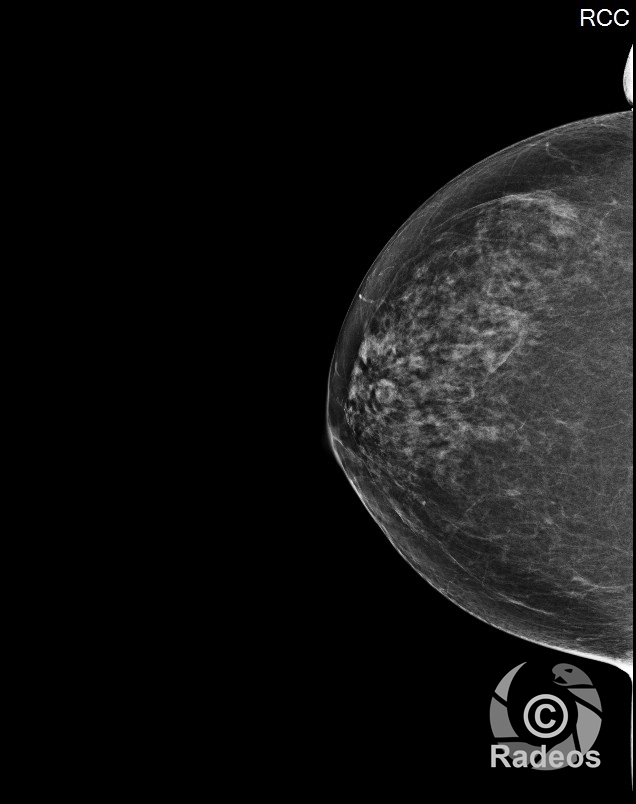

L’IRM mammaire combine analyse morphologique et paramètres fonctionnels pour optimiser la caractérisation des lésions.

IRM mammaire